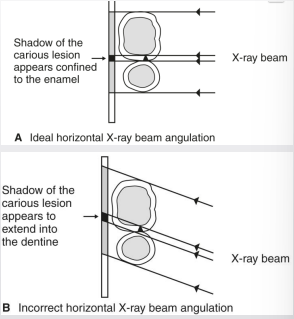

how is horizontal angulation a limitation of 2D imaging

change in angulation impacts ability to detect and stage carious lesions

what is horizontal angulation

contact overlap can obscure lesion and DEJ

changes of lesions relative to other structures→ DEJ and pulp